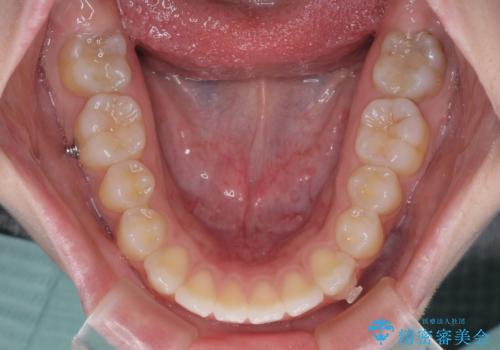

再矯正 開咬に後戻りした歯列をインビザラインで改善

- 矯正治療の後戻りを気にして来院された患者様です。

デコボコと上下前歯の隙間が気になるものの、しっかりと治療をしたいという意思はないとのことで、インビザラインの中でもアライナー数に制約のあるライトパッケージを用いて、治療できる範囲まで歯列を改善していくこととしました。

インビザラインは前歯部の開咬に効果的であることが多く、ライトパッケージにもかかわらず、十分満足のいく仕上がりとなりました。